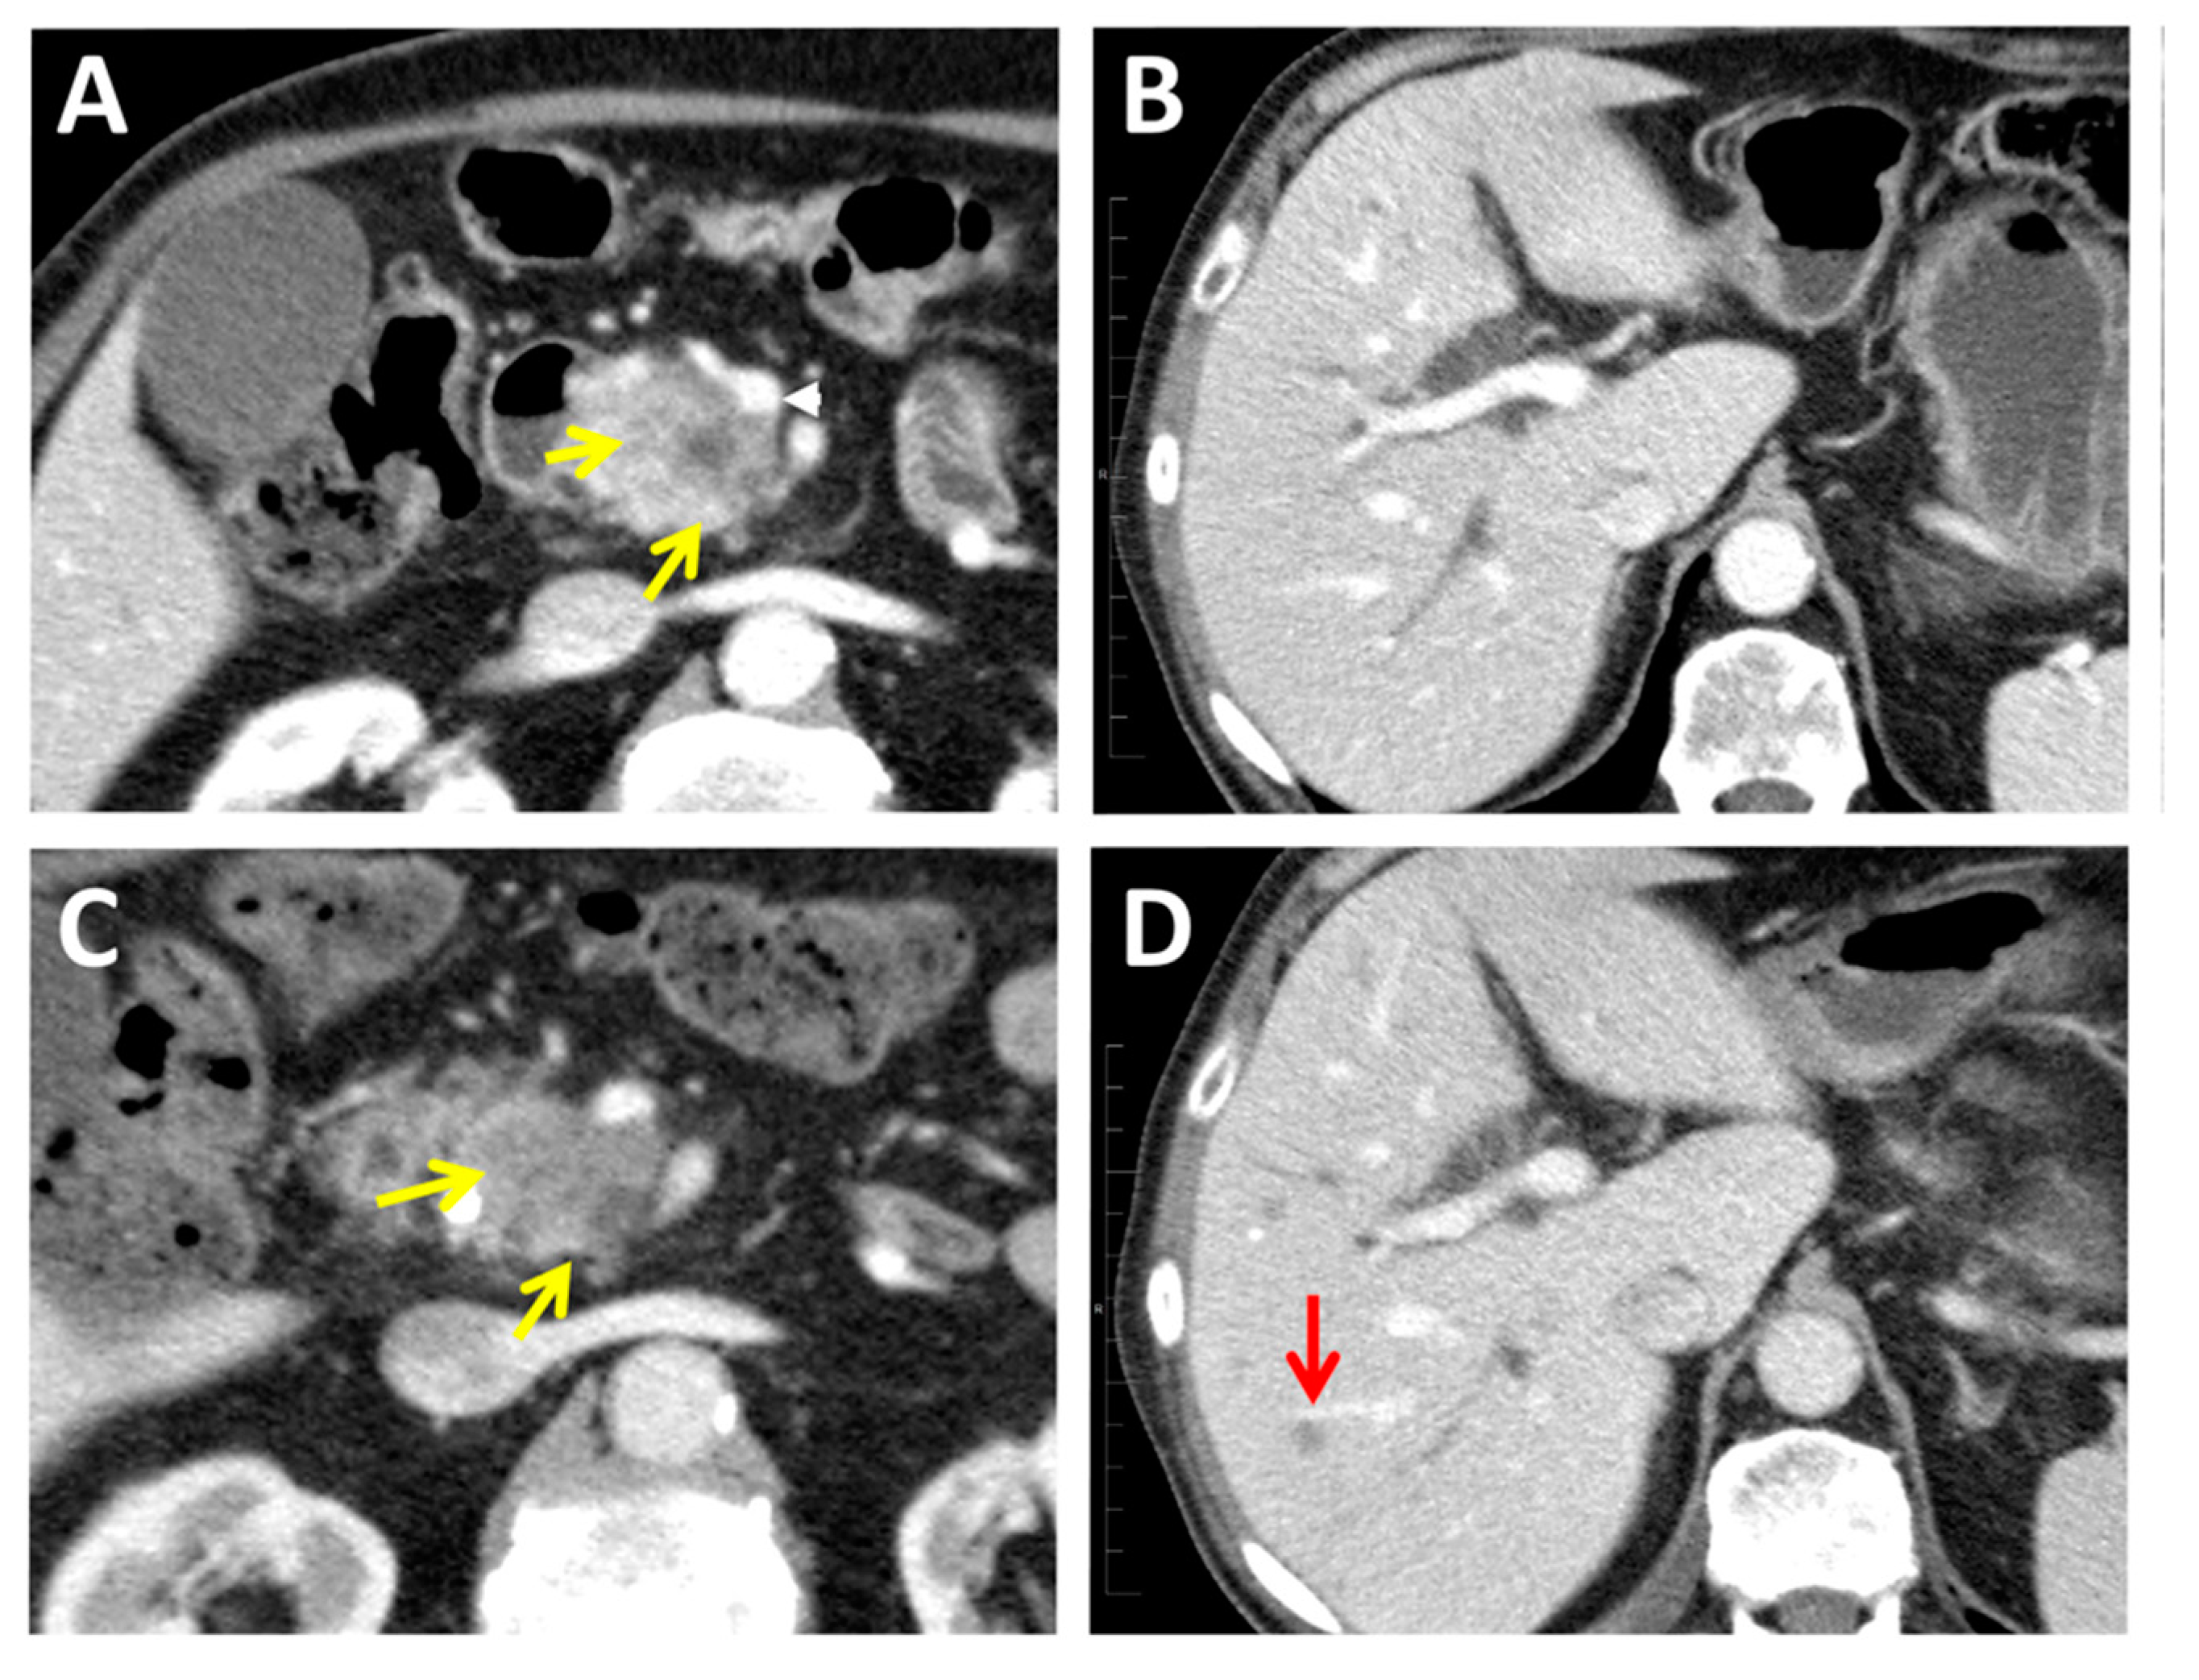

2.1. Computed Tomography

2.5. Chemotherapy and Radiotherapy Response